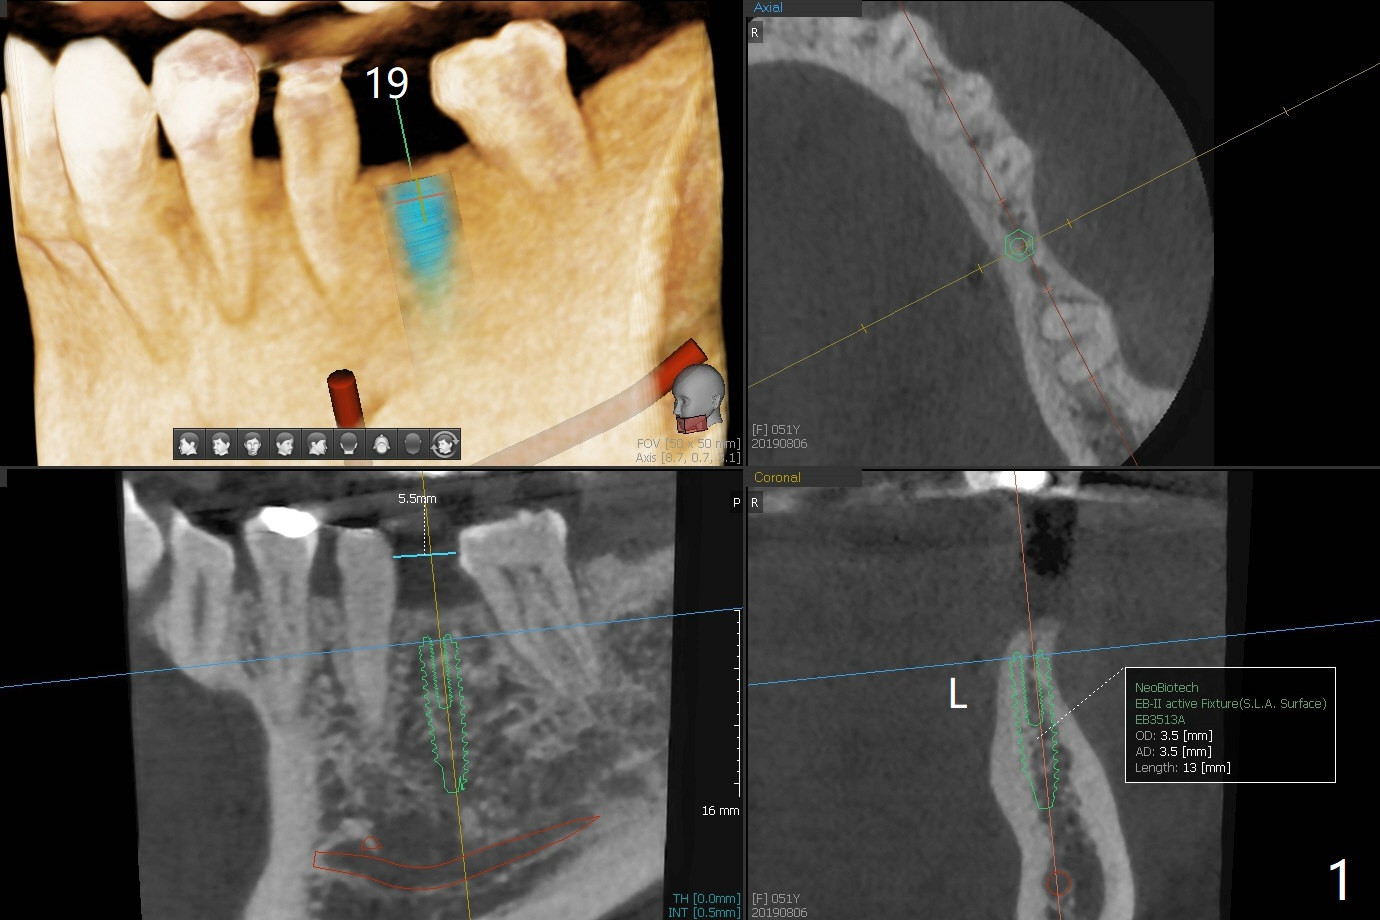

A 51-year-old woman has discomfort with #18-20 overcontoured FPD.  CT, taken after removal of the FPD, shows the narrow space and narrow ridge.  A 3.5 mm 2-piece (Fig.1) or 3.0 mm 1-piece (Fig.2,3) implant is indicated.  For ridge split, the ridge top will be trimmed with surgical handpiece and round bur (Fig.4).